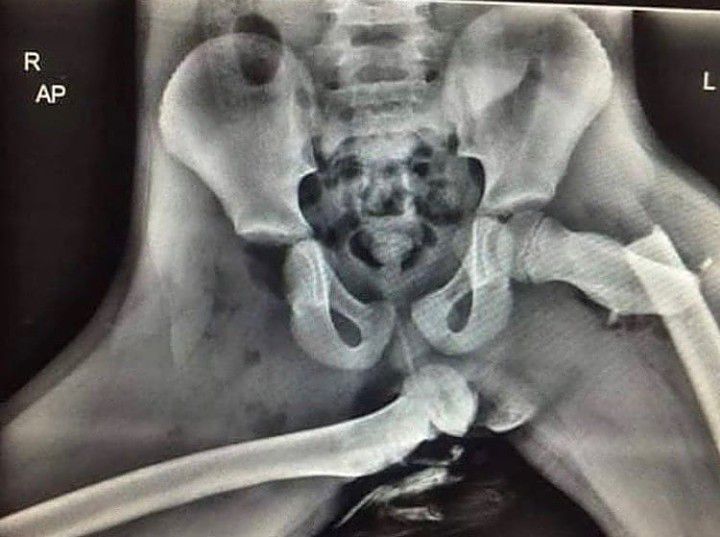

HORRIFYING X-RAY OF COMPLETE DISLOCATION !

Horrifying x-ray of complete this location as a result of putting legs on dashboard. By: https://www.instagram.com/p/CTbibGcsGOF/?utm_medium=copy_link